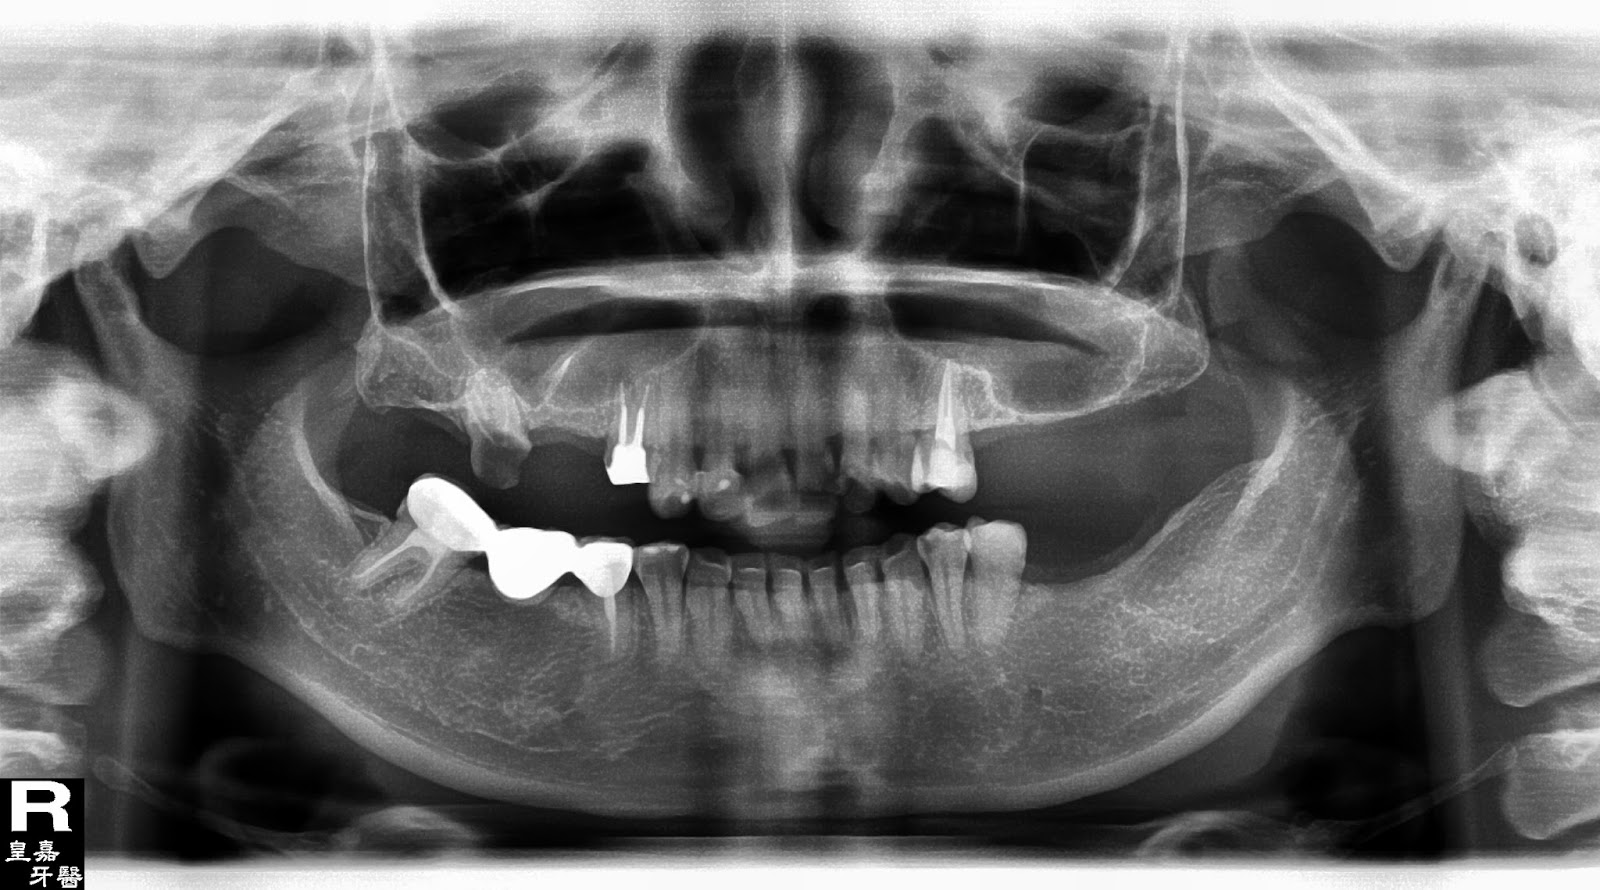

在經過口內與X光片檢查之後,莊小姐賴著說,不管啦,看是要多少錢,要把後面的牙齒做起來啦。我看了環口X光片,心裡默想,薄如蟬翼的鼻竇腔,困難與挑戰。

治療前全口X光片